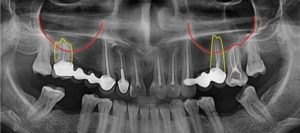

На фото: корни зубов у дна верхнечелюстной пазухи

- Близкое расположение корней моляров и премоляров. В некоторых случаях толщина костного слоя между зубными корнями и дном гайморовой пазухи может быть сравнительно большой — до 1 см, но у некоторых людей костная граница между этими образованиями совсем тонкая — не более 1 мм.

- Иногда корни первого и второго моляров располагаются в самой полости пазухи, отделяясь от нее всего лишь слоем слизистой оболочки.